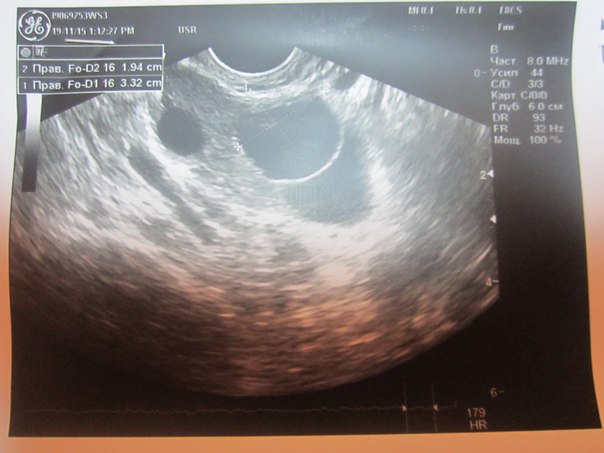

Я свой снимок УЗИ показала другому врачу. Она сказала,что никакая это не киста-это фолликулы. По размерам, должны скоро овульнуть,сделала тест на овуляцию-положительный. Через сутки сходила на УЗИ-была овуляция,нет кисты)))

33 на 19, но мерила она не отдельно каждый,а вместе,как двухкамерную кисту

Ну,если не брать замер 33,то фолликул у меня 19 на 19,вот он и овульнул.

28 на23 уж точно киста....у меня и больше росли,двухкамерные, кстати проходят сами!!!!. Ну или на каком то несерьезном лечении мне индометацин свечи назначали))).я вообще не поняла зачем и как..но прошли)... Сейчас у меня постоянно уже небольшие фолликулярные кисты и МФКЯ(а может и СПКЯ..но спкя не истинный конечно.а фукнкциональный..Хотя вот в этом месяце вроде есть овуляция..АМГ в августе зашкаливал...у меня это все длится после отмены КОК... Эндометрий у вас шикарный)

Эндометрий отличный. Мне когда делали стимуляцию тоже узист не мог определить двухкамерная киста или два ДФ рядышком друг возле друга. В итоге оказалось два ДФ, была овуляция.